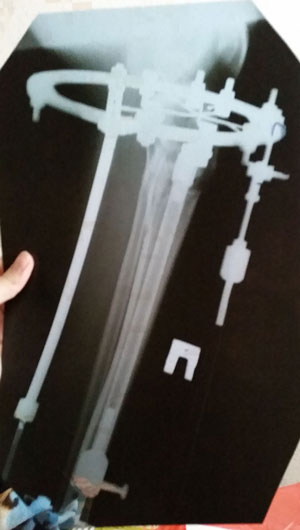

рентген в 90 дней с момента операции.

Ураа аЗдравствуйте, Ласка! По рентгену всё идёт хорошо, регенерат хороший, всё по плану. Через месяц будем готовиться к снятию аппаратов! (предварительно сделав рентген и выслав нам).